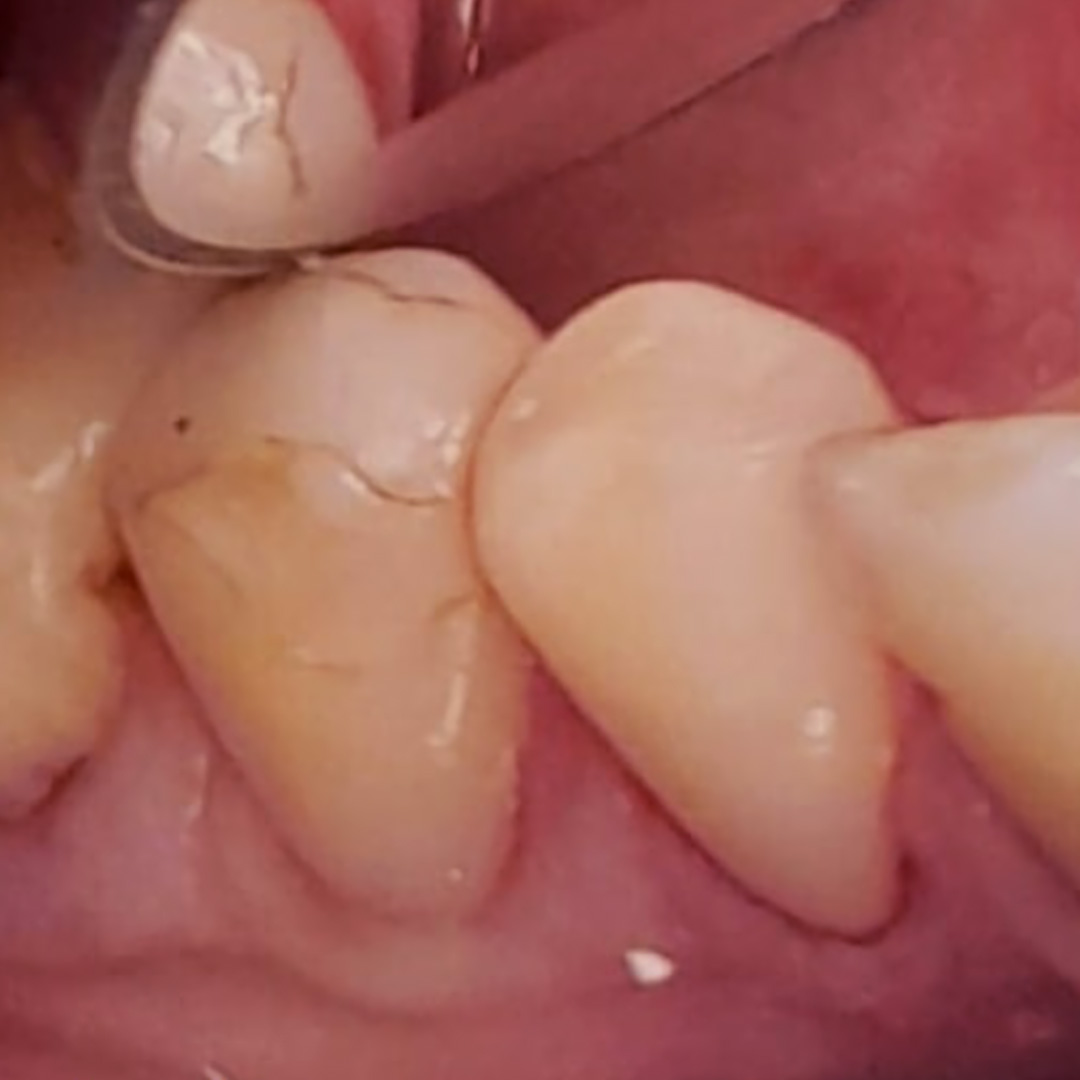

До и после лечения

Пациентка обратилась к стоматологу-терапевту с проблемой выпадения пломбы из премоляра нижней челюсти. Её также беспокоила резкая боль в зубе, которая возникает после принятия холодной пищи и напитков, но быстро проходит. Осмотр и диагностика позволили выявить у пациентки наличие глубокого кариеса зуба 44. Ей предложено лечение с установкой светоотверждаемой пломбы.

- установка и застывание светового композита Эстелайт;

- полировка и шлифовка зуба.